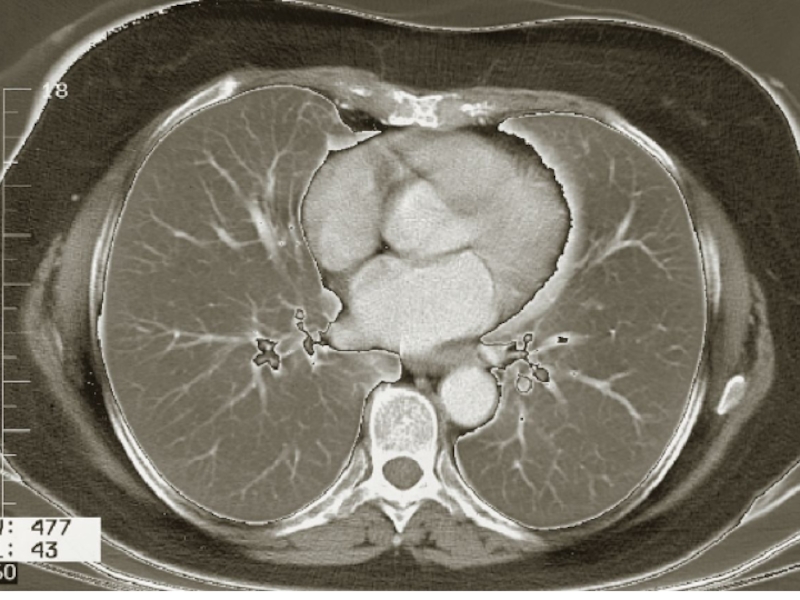

Слайд 87Томография и МРТ

Срез через верхнее средостение

Срез через нижнее средостение

Томография и МРТСрез через верхнее средостениеСрез через нижнее средостение